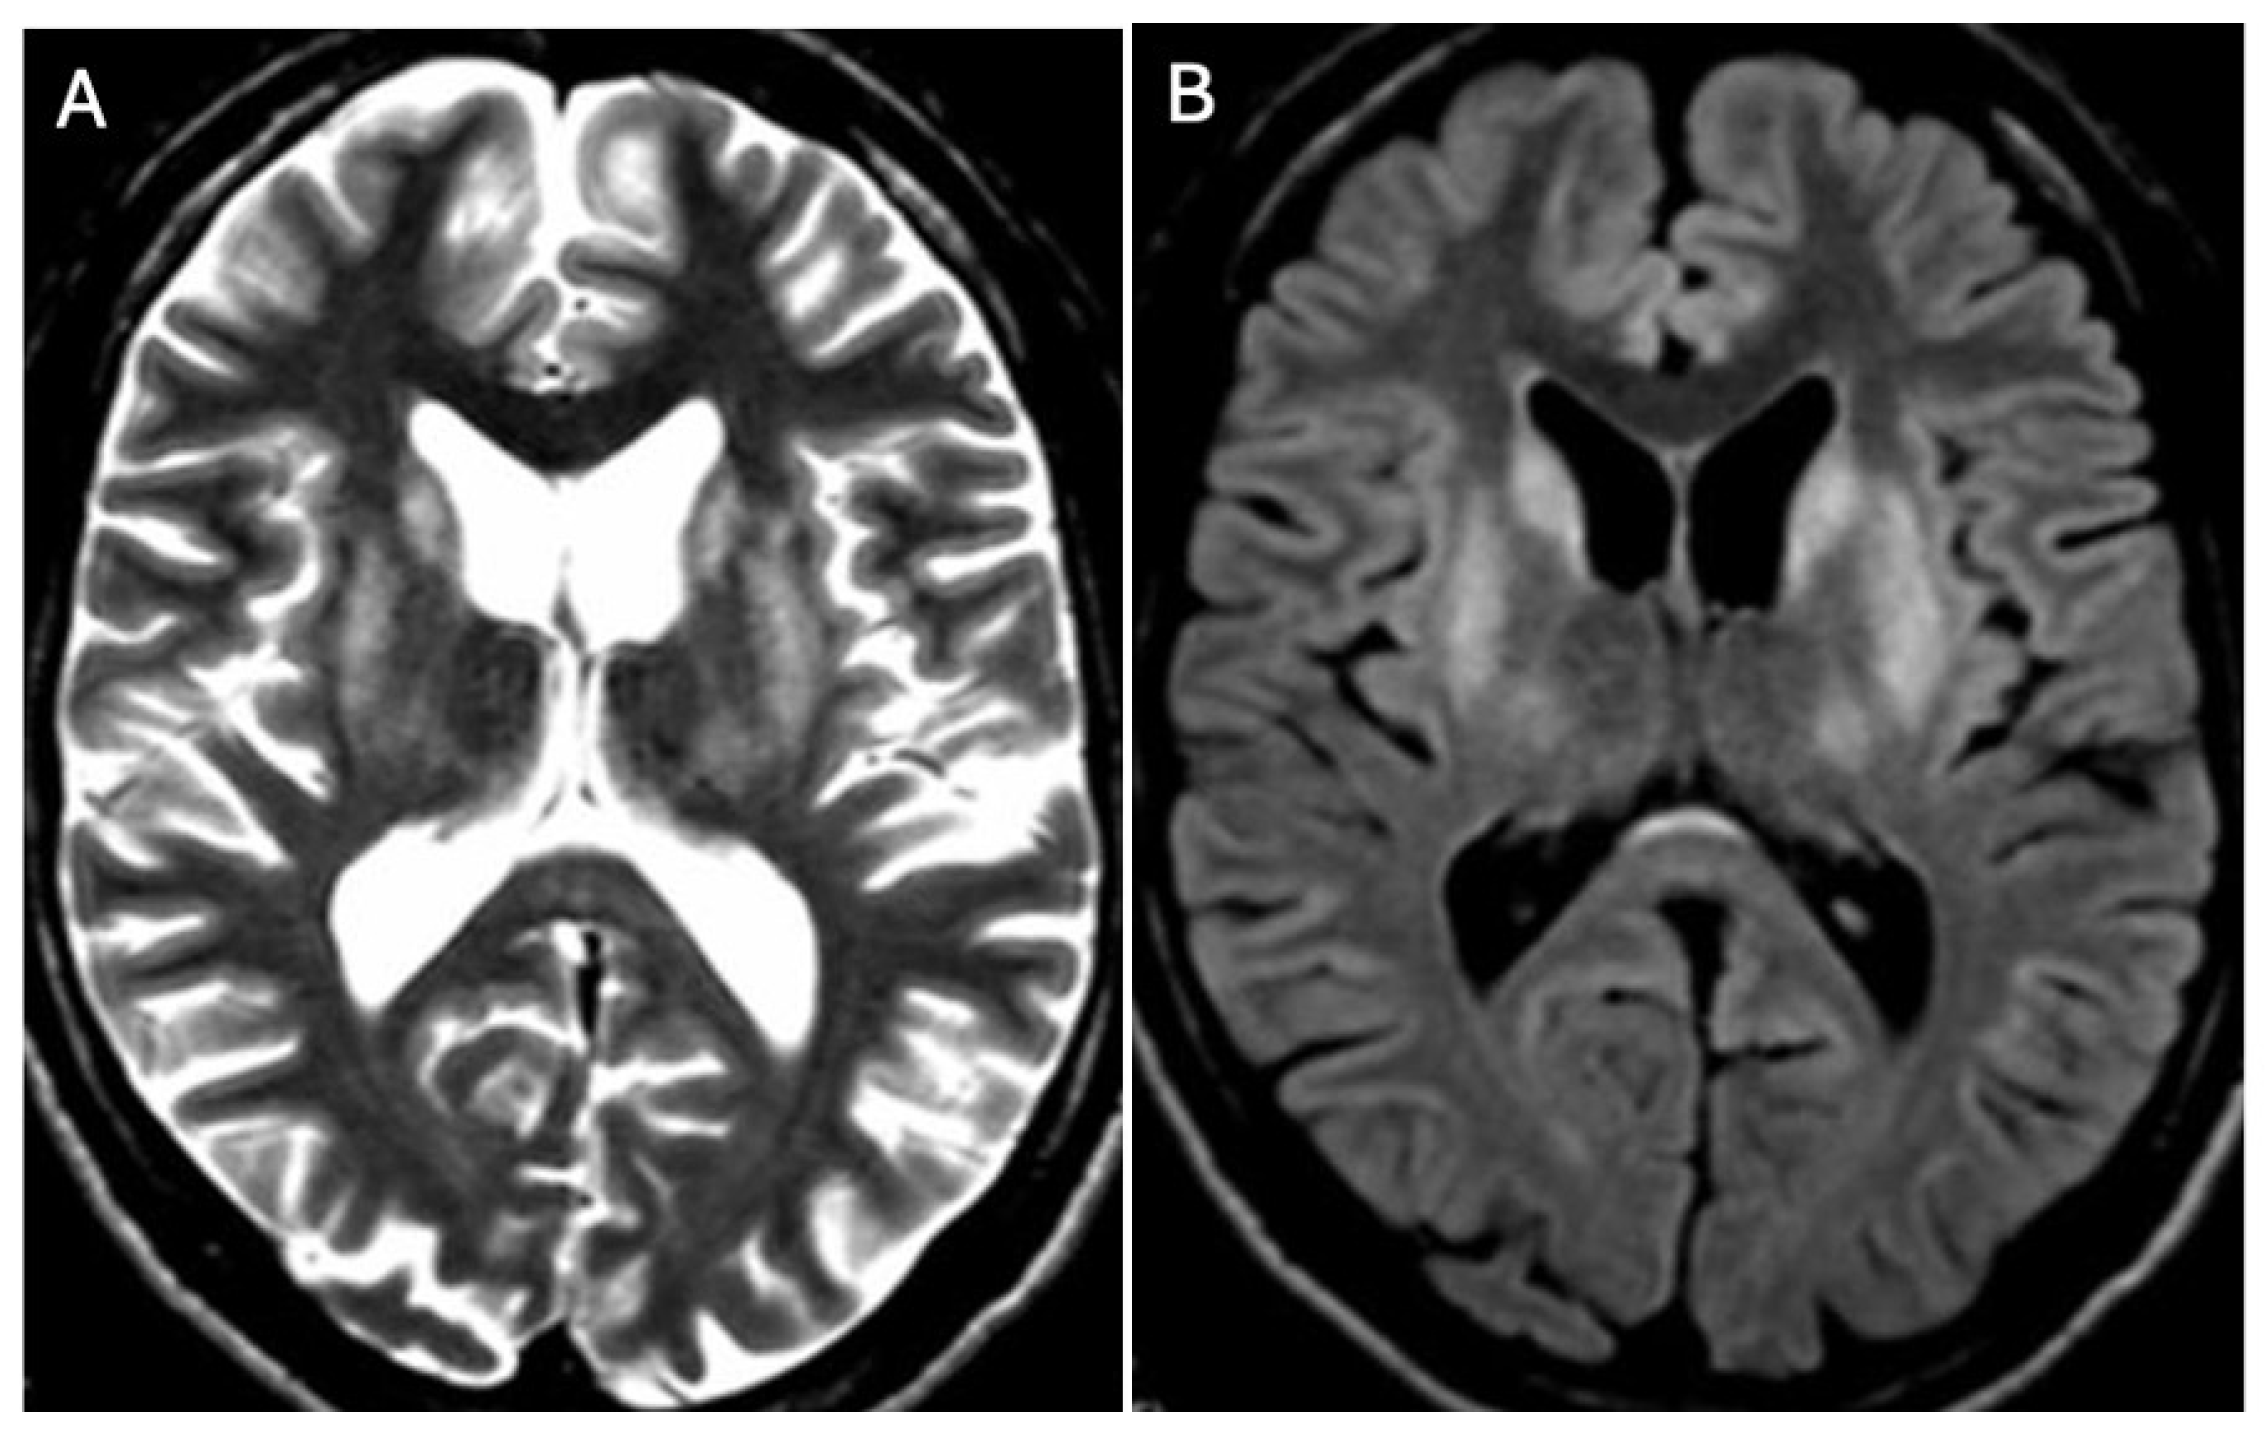

3.1. Classical Brain MRI Examination in WD Patients

3.2. Diffusion MRI in WD